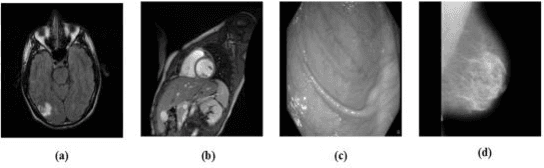

Abstract:Reversible image watermarking guaranties restoration of both original cover and watermark logo from the watermarked image. Capacity and distortion of the image under reversible watermarking are two important parameters. In this study a reversible watermarking is investigated with focusing on increasing the embedding capacity and reducing the distortion in medical images. Integer wavelet transform is used for embedding where in each iteration, one watermark bit is embedded in one transform coefficient. We devise a novel approach that when a coefficient is modified in an iteration, the produced distortion is compensated in the next iteration. This distortion compensation method would result in low distortion rate. The proposed method is tested on four types of medical images including MRI of brain, cardiac MRI, MRI of breast, and intestinal polyp images. Using a one-level wavelet transform, maximum capacity of 1.5 BPP is obtained. Experimental results demonstrate that the proposed method is superior to the state-of-the-art works in terms of capacity and distortion.